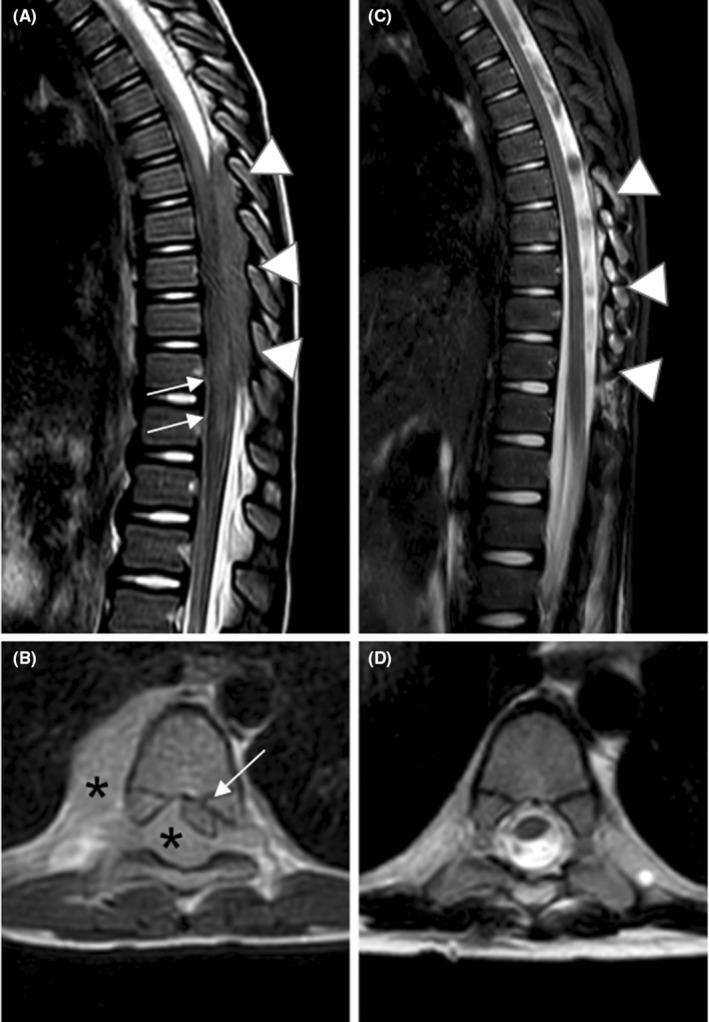

Pediatric non-Hodgkin lymphoma as a rare cause of spinal cord injury: When lymphoma hides in the canal.

Spinal cord compression in pediatric non-Hodgkin lymphoma (NHL) is a rare presentation with potential diagnostic challenges. We report on two pediatric patients with NHL who exhibited myelopathy signs as initial presentation. Considering NHL as a differential diagnosis in pediatric patients presenting with spinal cord compression is crucial for optimizing the outcome of these patients.